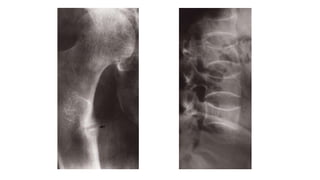

Osteosarcoma (osteogenic sarcoma)

Occurs mainly in the 5–20-year-old age group, but is

also seen in the elderly following malignant change in

Paget’s disease.

The tumour often arises in a metaphysis, most

commonly around the knee.

Florid spiculated periosteal reaction is present, the so-

called sunray appearance

The tumourmay elevate the periosteum to form a

Codman’s triangle